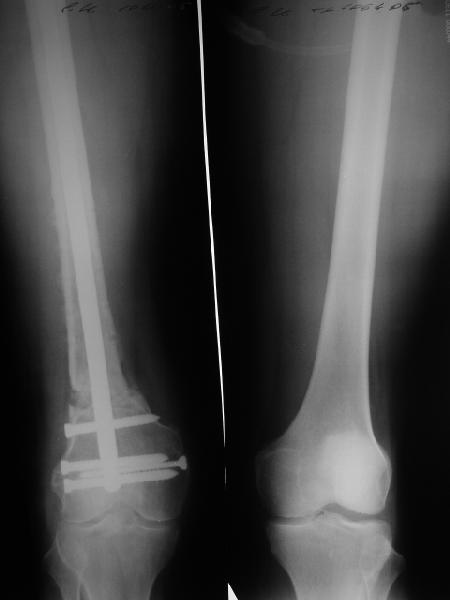

27 марта выполнено удаление блокирующих винтов (сломанный винт пришлось высверливать цапфен-бором), сломанного штифта (дистальный фрагмент удален через канал, образованный разверткой из коленного сустава - image 4),

рассверливание костно-мозгового канала, реостеосинтез штифтом UFN (при проведении штифта в дистальном отломке мы использовали поляризующий винт, диаметр штифта 10 мм). После операции в связи гемартрозом дважды (на 1 и 3 сутки) выполняли пункцию коленного сустава. Сейчас признаков скопления жидкости в полости сустава нет. Послеоперационные рентгенограммы - images 5, 6, 7.